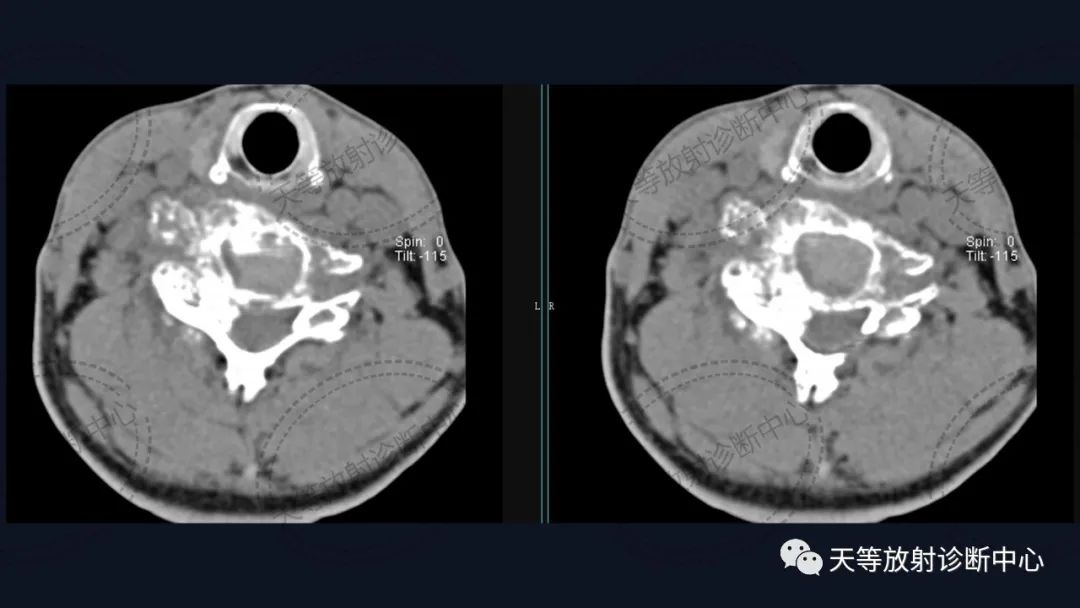

病例3:右下颌骨软骨肉瘤。本例 CT表现主要为骨质破坏、斑点状钙化及软组织肿块。

软骨肉瘤CT示病灶主体为软组织肿块,可合并内部钙化及邻近骨质破坏,病灶内钙化是软骨类肿瘤的相对特征性表现。